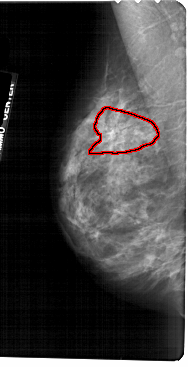

A_1724_1.LEFT_MLO

LEFT_MLO LINES 5491 PIXELS_PER_LINE 2806 BITS_PER_PIXEL 12 RESOLUTION 43.5 OVERLAY

FILE: A_1724_1.LEFT_MLO.OVERLAY

TOTAL_ABNORMALITIES 1

ABNORMALITY 1

LESION_TYPE CALCIFICATION TYPE PLEOMORPHIC-FINE_LINEAR_BRANCHING DISTRIBUTION SEGMENTAL

ASSESSMENT 4

SUBTLETY 3

PATHOLOGY MALIGNANT

TOTAL_OUTLINES 1

BOUNDARY